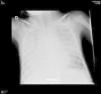

A los 2 meses presentó de nuevo astenia de forma brusca que motivó una nueva consulta en urgencias. En la exploración física presentaba buen estado general con taquipnea, roncus bilaterales y auscultación cardiaca con soplo sistólico III/VI con latido no hiperdinámico. Presentó Hb 4,5 g/dl sin parámetros de hemólisis asociados por lo que se transfundió un concentrado de hematíes y se realizó una nueva radiografía de tórax que mostró nuevamente infiltrados pulmonares difusos. Ante este segundo episodio de infiltrados pulmonares difusos junto con el tercero de anemia aguda grave, se decidió realizar una tomografía computarizada (TC) torácica (fig. 2) que mostró opacidades bilaterales parcheadas y simétricas en vidrio deslustrado de predominio en campos posteriores y basales. Con la sospecha de hemorragia alveolar difusa se realizó una fibrobroncoscopia con lavado broncoalveolar (LBA) donde se observaron los característicos siderófagos, que confirmaron el diagnóstico. Se completó el estudio para descartar causas secundarias de hemorragia alveolar difusa (ecocardiograma, sedimento de orina, autoanticuerpos -ANA, ANCA, factor reumatoide, anticuerpos antimúsculo liso- y estudio del complemento -C3 y C4) que fueron normales y de posibles precipitantes de una HPI (marcadores de celiaquía e IgE específica frente leche de vaca, caseína, alfalactoalbúmina y betalactoglobulina) que resultaron negativos. Con el diagnóstico de HPI se inició tratamiento con metilprednisolona intravenosa (2 mg/kg/día) y N-acetilcisteína (300 mg/12 h) asociada al soporte respiratorio. Recibió el alta sin otras complicaciones.

La radiografía de tórax suele mostrar imágenes simétricas de predominio perihiliar y en las bases siendo hasta en un tercio de los casos normales. En la TC torácica son características las imágenes en vidrio deslustrado de predominio en regiones posteriores y basales de ambos campos pulmonares semejantes a las que se encontraron en nuestro paciente. En los estudios de función pulmonar es característico un patrón restrictivo con un test de difusión de monóxido de carbono aumentado durante el episodio agudo4. Para la confirmación diagnóstica de hemorragia alveolar difusa es preciso realizar una fibrobroncoscopia con LBA en la que característicamente se observan, a partir del quinto día de sangrado, hasta un 50% de siderófagos. El diagnóstico final de la HPI es un diagnóstico de exclusión pues siempre hay que descartar una causa secundaria de la hemorragia alveolar siendo la más frecuente en pediatría las alteraciones cardiovasculares5,6, aunque también hay que descartar aquellas vasculitis que cursan con capilaritis pulmonar (enfermedad de Wegener, síndrome de Goodpasture, etc.) y que, según algunos autores, pueden hacer obligatorio realizar una biopsia pulmonar.